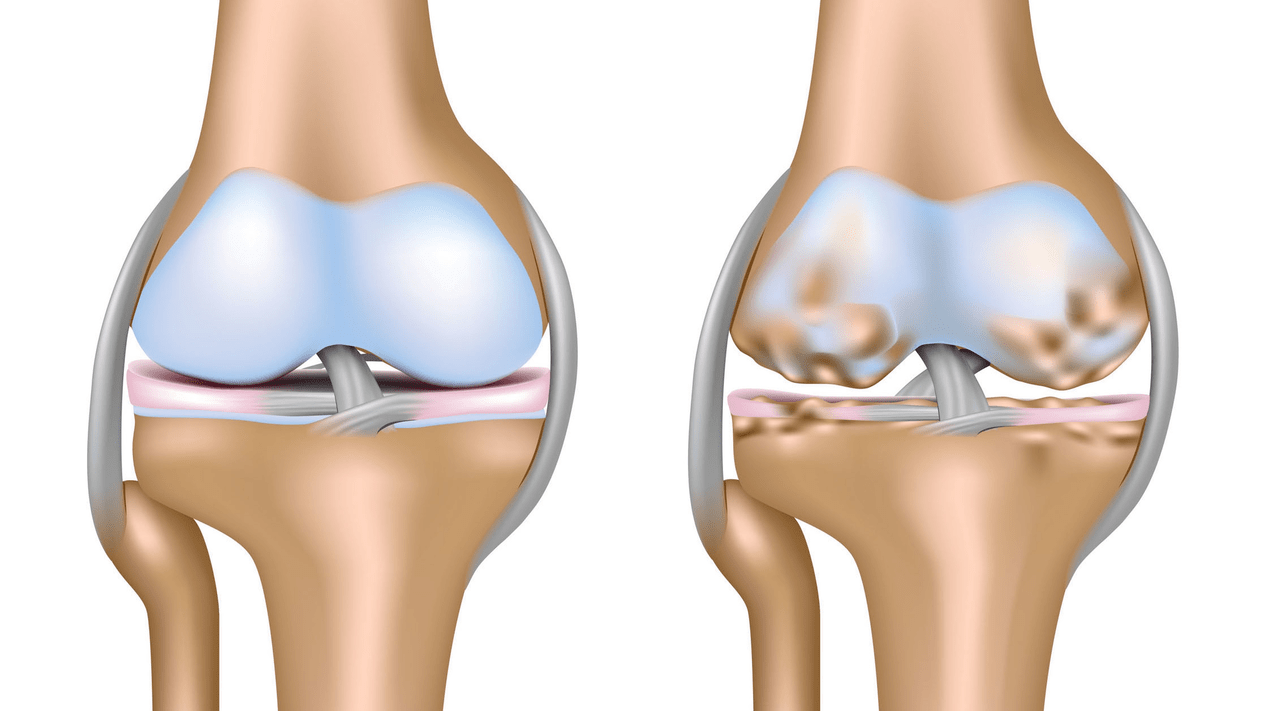

Arthrosis of the knee joint (gonarthrosis)a progressive chronic disease of the knee joints, during which the cartilaginous part (the articular surfaces of the femur and tibia) means damage, thinning and damage, as well as damage to the bone under the cartilage.Examinations (arthroscopy and MRI) confirmed that, in addition to damage to the articular cartilage, the meniscus and the articular membrane are also involved in the process.Gonarthrosis is one of the most common orthopedic pathologies.It has synonyms - osteoarthritis (OA), deforming arthrosis.The disease is an important socio-economic problem, as it is widespread and, due to the constant pain, significantly impairs the quality of life of the patients, in addition, it becomes a cause of high disability.

Until the mid-eighties of the last century, there was no uniform definition of the disease.It was not until 1995 that the osteoarthritis committee of the American College of Rheumatology characterized the disease as the result of mechanical and biological factors that lead to an imbalance between the breakdown and synthesis of the extracellular matrix of articular cartilage.As a result, disintegration and degeneration of fibers occurs, cracks, osteosclerosis and compaction of the cortical layer of subchondral bone, osteophytes grow and subchondral cysts are formed.

During arthrosis (osteoarthrosis), in addition to the progressive destruction of the cartilage, loss of elasticity and shock-absorbing properties, the bones are gradually involved in the process.Under load, sharp edges (exostoses) appear, which are mistakenly considered "salt deposits" - salt deposits do not occur in classic arthrosis.As arthrosis progresses, it continues to "eat away" the cartilage.Then the bone is deformed, cysts are formed, all the structures of the joint are affected, the leg bends.